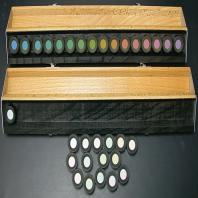

- eFig. 9-22 - Les pions sont sortis et mélangés de façon aléatoire. Le patient doit les reclasser en partant du premier pion qui est fixe (100 Hue)

- eFig. 9-23 - Ce schéma en cercle ouvert permet la visualisation directe de l'axe de confusion